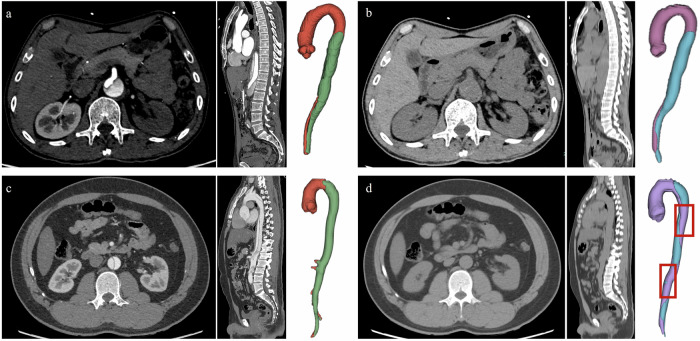

Example cases for visualization

Our deep-learning framework was conceptualized to generate the involved range for confirmed cases of AD. The Figs. 5a, b and 6a, b demonstrate the good performance of our model in detecting AD and non-AD cases, and provide direct visualization of the true and false lumen. However, several cases with poor performance also exist (Figs. 5c, d and 6c, d). Specific descriptions are present in the figure legends.

Fig. 5.

The examples of good and bad segmentation cases for AD. a, b A 64-year-old man, admitted to the hospital with back discomfort for one month. The CTA images and the 3D-volume reconstruction (VR) view of the aorta show the dissection of the aorta (a). The non-contrast images at the same level and the 3D-VR show good segmentation of true/false lumens on non-contrast images (b). The ground-truth false lumen volume is 107,282 mm3 and the predicted false lumen volume is 134,885 mm3. The Dice coefficient is 0.817. c, d A 33-year-old man, admitted to the emergency department with severe chest pain for 10 min. The 3D-VR of NCCT images presents a not-satisfactory segmentation (d compared with c). The standard false lumen volume is 155,658 mm3 and the predicted false lumen volume is 97,159 mm3. The Dice coefficient is 0.580

Fig. 6.

The examples of good and bad segmentation cases for non-dissection. a, b A 37-year-old man, admitted to the emergency department with back discomfort for several days. There is no positive finding in contrast-enhanced CTA images (a). The 3D-VR of the aorta in the right part shows that the false volume is 0 mm3 (b), which indicates that there is no AD. c, d A 53-year-old man, admitted to the emergency with a fall for 5 h. There is no positive finding on contrast-enhanced CTA images (c). However, the positive false lumen is detected with our deep learning framework (d)